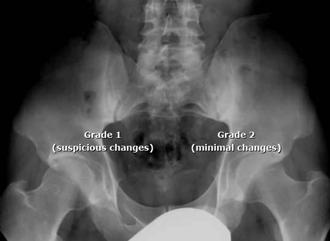

♦ Sacroileítis en la radiografía (grado 2 bilateral o grado 3-4 unilateral) o resonancia magnética (edema de médula ósea u osteítis) más ≥ 1 característica de espondiloartritis a continuación, O

Figura 14. Sacroileitis

Radiografías simples de la columna y la pelvis como técnicas de imagen iniciales